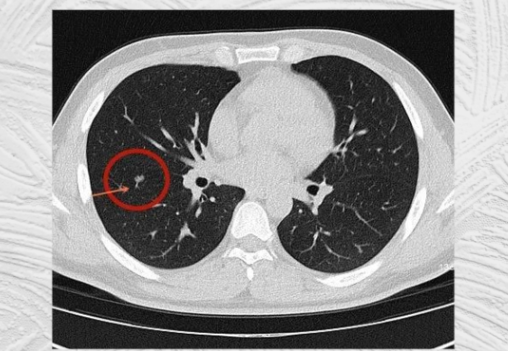

口罩事件之后,很多人患上了肺结节,而且很多还患上了毛玻璃结节(被认为是癌变率极高的一种类型),目前对于肺结节而言,常规的抗生素和激素疗法治疗效果非常有限。手术治疗肺结节,效果“立竿见影”,但是对自身体的脏腑损伤比较大,很多情况下留下难以治愈的后遗症,如肺部刺痛、荨麻疹等,最重要的是,手术无法改善身体大环境,切除之后还复发,而且对于高风险的肺结节手术治疗有造成转移风险增大。